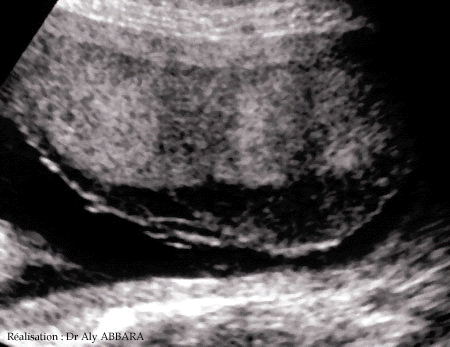

Hématome de la face fœtale du placenta à 27 semaines d'aménorrhée